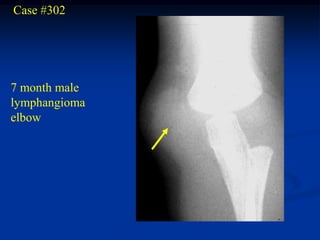

Case #302

7 month male

lymphangioma

elbow

Coronal T-1 MRI

Axial T-2 MRI

Case #302 7 monthmale lymphangioma elbow